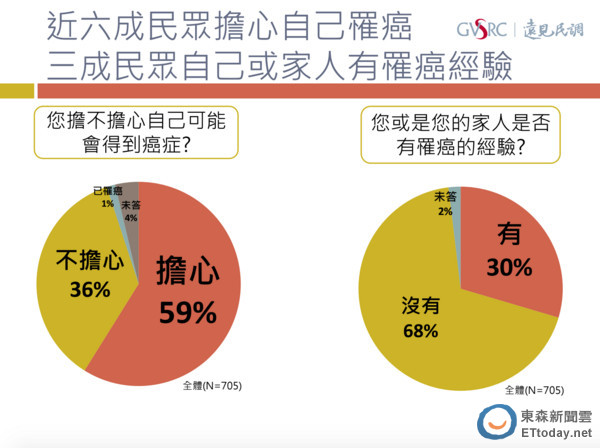

癌症長年盤據國人十大死因首位,衛福部今年4月發布的「2012年癌症登記報告」顯示,台灣每5分26秒就有一人罹癌,快轉的速度較2003年快了1.6倍。即使癌症治療的武器不少,新藥推陳出新,乳癌、大腸癌、子宮頸癌預後良好,但遠見民調中心的最新調查發現,有近6成(58.9%)的受訪者,擔心自己會得到癌症。

癌症不一定是絕症,但抗癌路漫漫,過程艱辛,針對三成(29.6%)本身或家人有罹癌經驗的人,調查也詢問他們最困擾的事?結果缺乏人力照顧(39.1%)排第一,其他依序為:擔心病情惡化或死亡(38.4%)、醫療費用太高(36.8%)、擔心治療副作用(32.5%)等等。